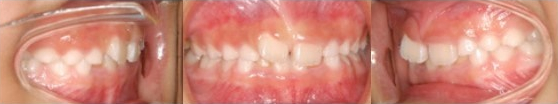

Pre-Ortho type 1. 과개교합 전용

8세여아, 프리올소 착용 4개월 후

첫 번째는 과개교합 전용 타입인데요.

앞니가 깊게 물린 과개교합에 치열이 심하게

틀어져있지만 이를 착용함으로써

올바른 성장을 유도하고, 2차교정에 들어갈 때

유리하게 적용됩니다.